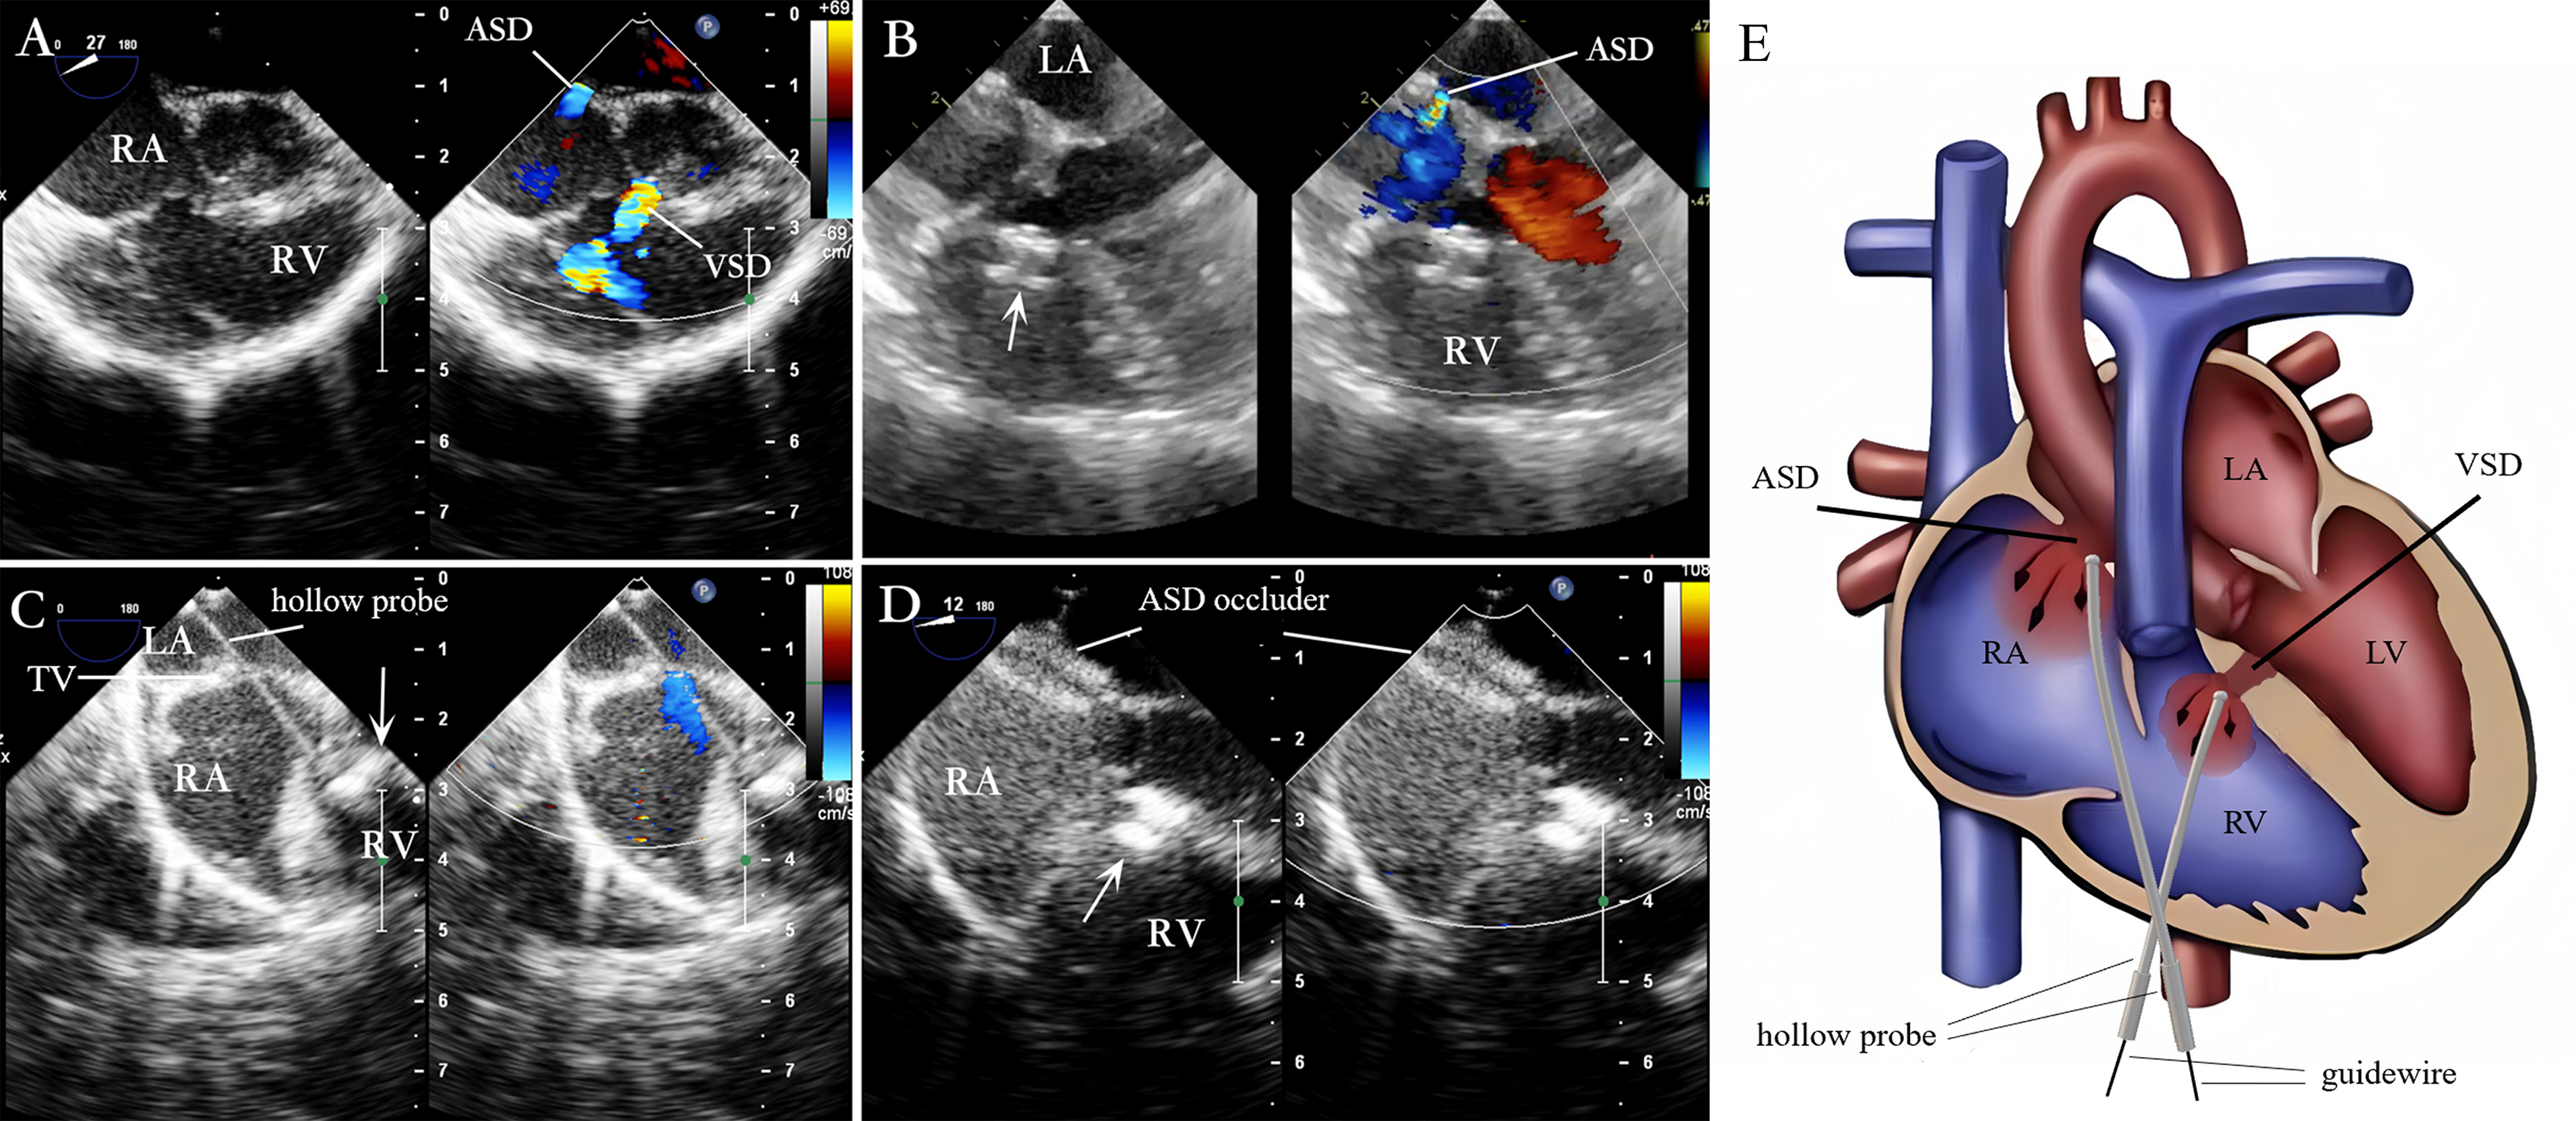

Under TEE guidance for evaluating VSD and ASD (Fig. 4A), a guidewire, delivery sheath, or hollow probe was used to pass through the VSD. Then, the VSD occlusion was completed (Fig. 4B). Then, the delivery catheter was adjusted, or the hollow probe was re-inserted gently. Next, it was cautiously advanced through the tricuspid valve as it opened to avoid damaging the valve (Fig. 4C). The delivery catheter was passed through the ASD to enter the left atrium before a guidewire was inserted to pass through the ASD into the left atrium; the ASD delivery system was advanced along this guidewire. The occluder was placed to complete the occlusion (Fig. 4D). The position and morphology of the ASD occluder, the RS, and the regurgitation of adjacent valves were evaluated. Once the TEE confirmed the position of the ASD occluder to be satisfactory, the delivery system was removed. The schematic diagram of the procedure is shown in Fig. 4E.

Fig. 4. Lower mini-sternotomy perventricular approach for simultaneous occlusion of VSD combined with ASD. (A) VSD combined with ASD. (B) After puncturing the RV wall and occluding the VSD, the four-chamber heart view illustrates the ASD. (C) After occluding the VSD, the straight hollow probe passes from the RV through the TV to the RA and is adjusted to pass through the ASD. (D) A guidewire and delivery sheath are inserted along the probe hole to complete the ASD occlusion. (E) The hollow probe is directed towards or through the VSD via the RV puncture site for VSD occlusion. Then, through the same right ventricular puncture site, the hollow probe is directed through the TV into the RA, towards or through the ASD, for ASD occlusion. Note: arrow = VSD occluder.